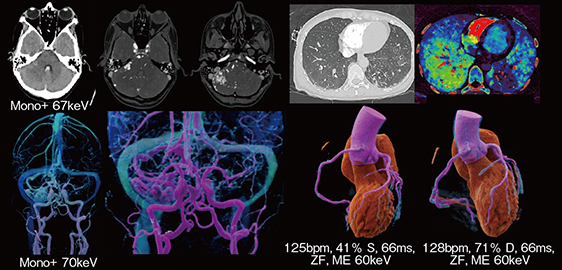

PCD-CTは空間・時間・コントラスト分解能が高く,血行動態評価に有用である。非心臓疾患の超高速撮影では,冠動脈起始部や大動脈の真腔・偽腔の血流も明瞭に描出可能である(図5)。

また,PCD-CTではSpectral解析を用いることで,造影剤量を40mLまで低減してもステントや動脈閉塞,微細な側副動脈,石灰化の詳細な描出が可能である。

図5 超高速撮影による心血管の描出

NAEOTOM Alphaは,3機種いずれも,すべての患者に同等の画像を提供でき,疾患や緊急度に応じた適切な撮影が可能である。なかでも,特に高心拍患者における心臓画像診断において,Dual Sourceによる高い時間分解能を生かし,NAEOTOM Alpha.PeakおよびNAEOTOM Alpha.Proを活用している。